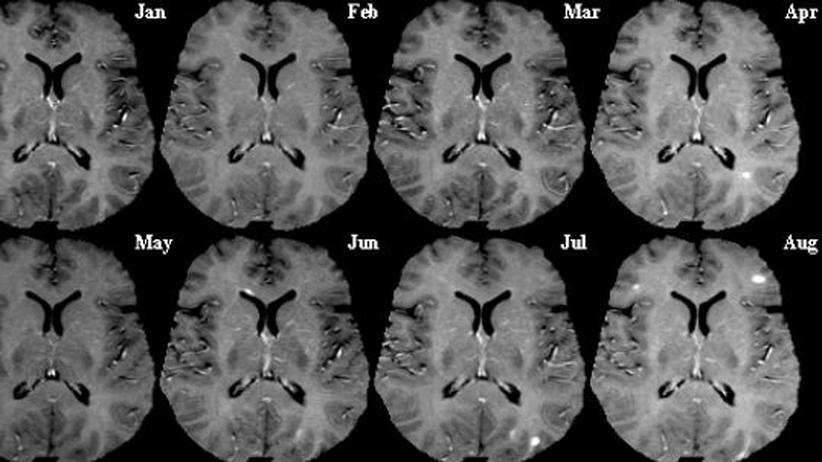

Heute kann man Multiple Sklerose-Patienten viel besser ...

Heute kann man Multiple Sklerose-Patienten viel besser ... from s3-eu-west-1.amazonaws.com